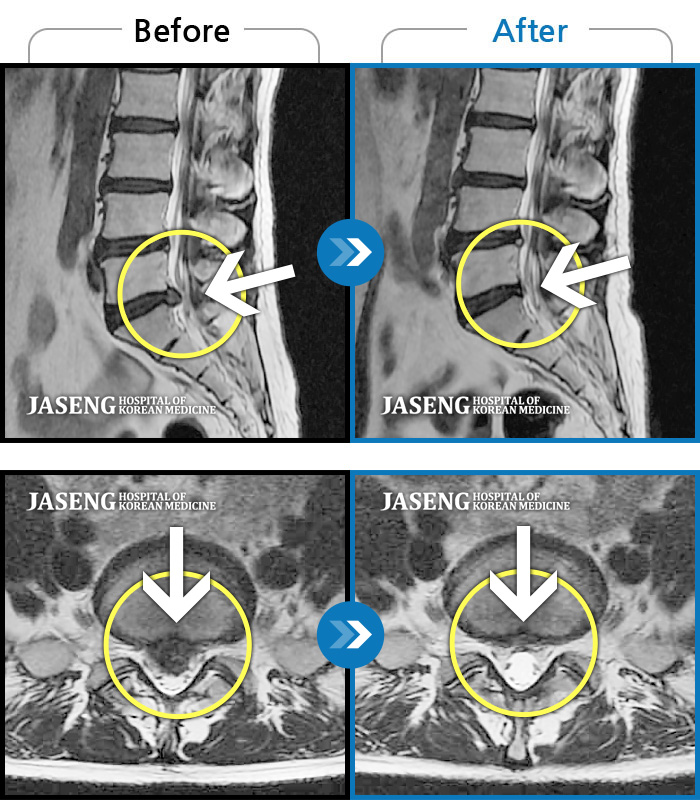

허리디스크

안산 · 김민수 원장

발목의 힘이 떨어져서 절뚝거리면서 걸었다.

촬영시기

2022.01.03 ~ 2024.07.31

2024.08.09